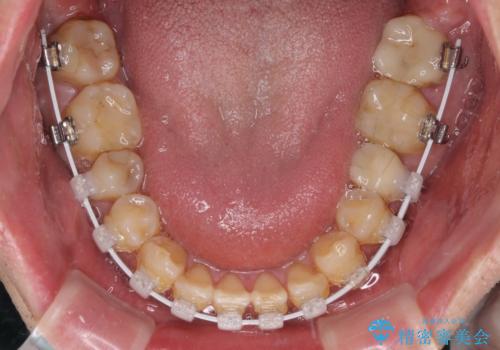

- 虫歯が多く、セラミッククラウンにより虫歯治療を行っている途中で矯正治療をしたいとのことで来院された患者様です。

上顎前歯が舌側に転位しており、なるべく早く楽に矯正したいとのことで、ワイヤー矯正を行うこととしました。

虫歯治療途中の歯は仮歯が装着されていたため、そのまま矯正治療を行い、矯正後に補綴治療を行うこととしました。

インビザライン矯正では苦手とする舌側転位した前歯をスムーズに改善することができました。

矯正治療により歯磨きがしやすくなったので、虫歯予防のセルフケアが行いやすい環境となりました。